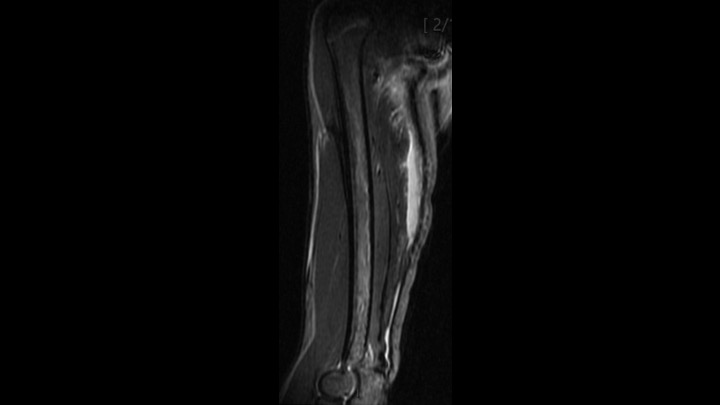

15 y/o running pain for 3 weeks. Flexor strain while running track.

15 y/o running pain for 3 weeks. Flexor strain while running track. Read More »